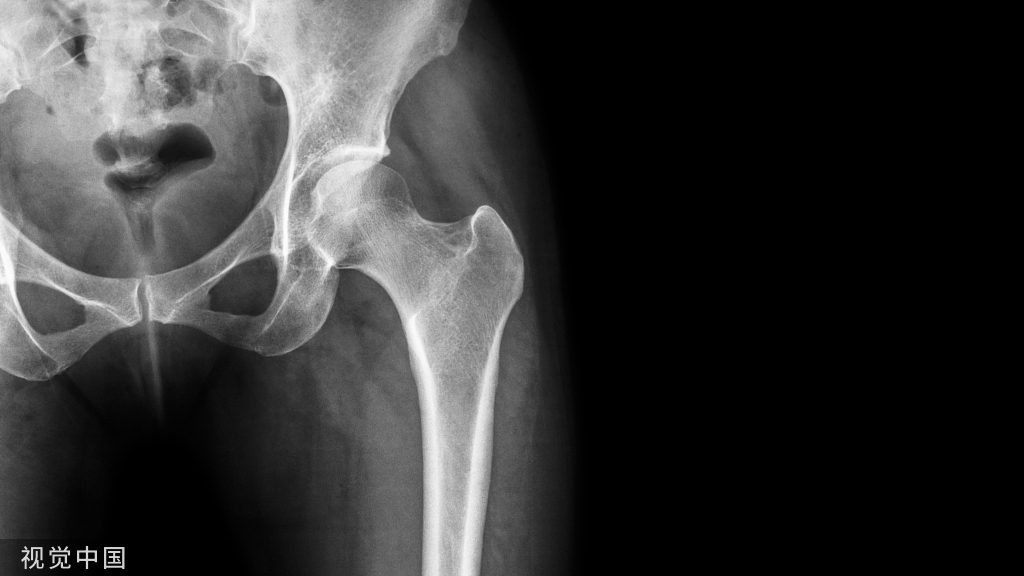

随着医疗技术的不断进步,骨科内固定装置作为治疗骨折的重要手段,在市场上存在多种选择。其中,进口和国产的内固定装置成为医生和患者关注的焦点。本文将探讨进口和国产骨科内固定装置的优缺点,以便为医生和患者提供更全面的信息。